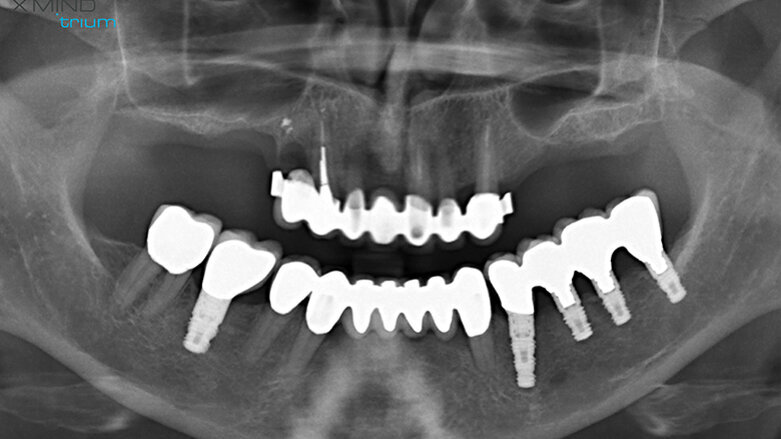

Figure 1 shows a split-mouth case with a bilateral INTRALIFT procedure: after a small crestal “booklet”-flap of approx. 7x7mm is detached, the sinus floor is safely opened with ultrasound Piezotome tips (Figs. 2 & 3), the sinus membrane then detached by the hydrodynamic cavitation effect of the Piezotome-tip TKW5 plugged into the approach canal (Figs. 4 & 5) and the subantral scaffold filled with 2cm of randomly assigned biomaterial (Figs. 6 & 7), followed by wound closure (Fig. 8). After a mean healing period of 8,4 months X-Mind trium CBCT scans were performed, the digital setup of the future bridge constructed with the AIS 3D app and the bone density determined in the sinus-lift site around a virtual implant (Fig. 9). Standardised implants (4mm in diameter and 12mm in length) were then inserted in the position of the virtual implant and insertion torque values (ITV) measured intra-surgically (test groups; Fig. 10). A total of 27 patients with sufficient native subantral crestal bone (min. crest width: 6 mm, height: 12 mm) were screened by X-Mind trium CBCT for bone density with the virtual implant (Fig. 11), the standardised implant inserted and the ITV recorded (control group). Figure 12 depicts the final result after implant insertion in the patient case shown in Figures 1–9.

As can be seen in Fig. 13, the mean CBCT bone density values in Hounsfield units (HU) at the implant site differed significantly (p <0.05) between all four test groups and the control group. The precise numerical HU values are “translated” by AIS 3D app software and are also colour-coded for easier interpretation at first glance: the brighter the green the CBCT voxel matrix shows around the virtual implant, the higher the bone density, with a virtual neutral threshold of 500 HU. Contrary, the more reddish the CBCT voxel matrix around the digital implant is depicted, the worse the biomechanical bone quality (Fig. 14). The corresponding insertion torque values (ITV) of the inserted standardised implant measured at the location of the transcrestal INTRALIFT approach (Fig. 2) also differed significantly between all test groups and the control group. Figure 15 depicts the cumulative result of the correlation between HU and ITV values for all test groups and the control group.